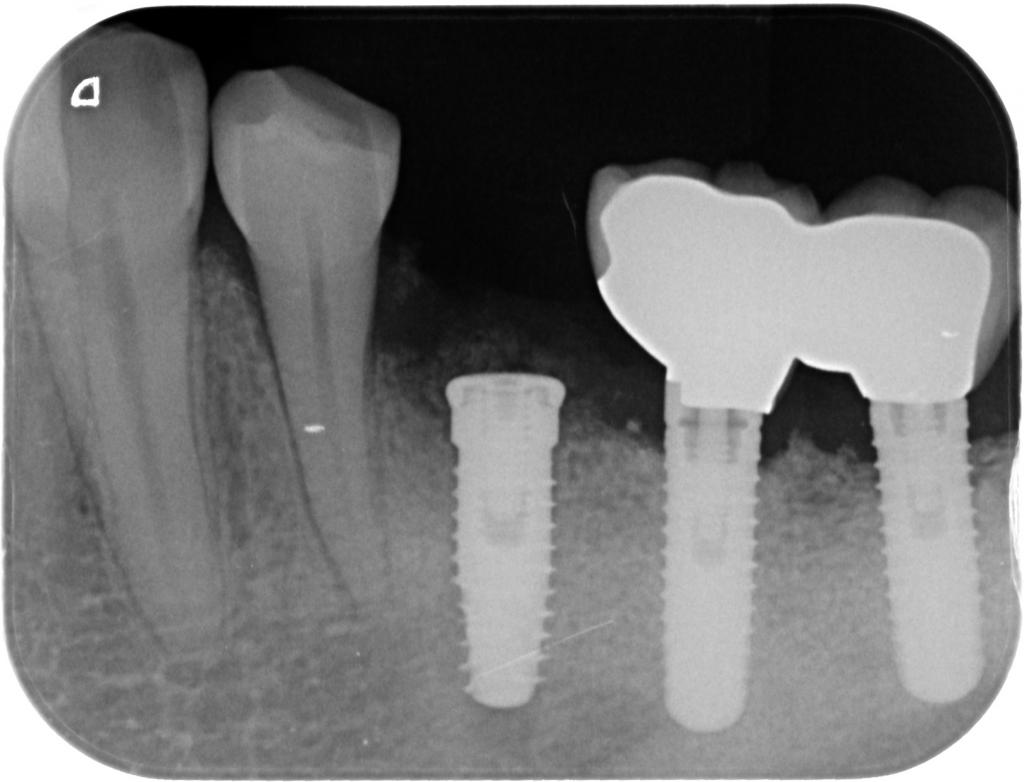

- 術後のレントゲン写真です。

20年ほど前に行ったインプラント部も骨の吸収も見られず、問題なく機能しています。